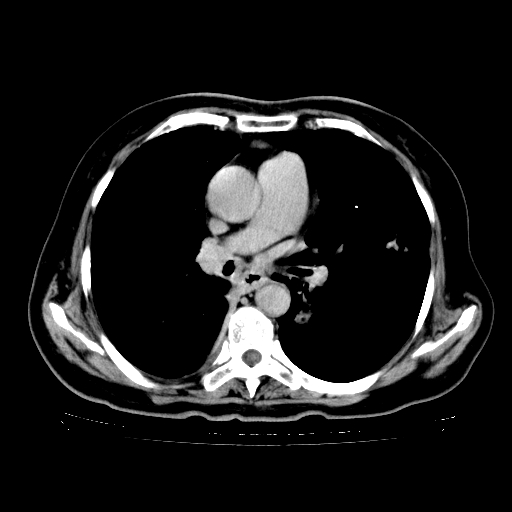

标题: CT23067:女,70岁,咳嗽、咳痰一个月,低热一周。 [打印本页]

女,70岁,咳嗽、咳痰一个月,低热一周。

1.左上肺结核,部分纤维化。右肺中下叶部分肺不张,内见液化、坏死及点状钙化,右中下叶支气管壁增厚、管腔狭窄,见多个点状钙化,结合临床考虑支气管内膜结核,建议痰检查抗酸杆菌并参考血沉。两肺多个小圆点状高密度灶,境界模糊,多考虑结核肺内播散。但本人年龄较大首先应支气管镜检以除外右肺癌。

2.胸主动脉夹层。